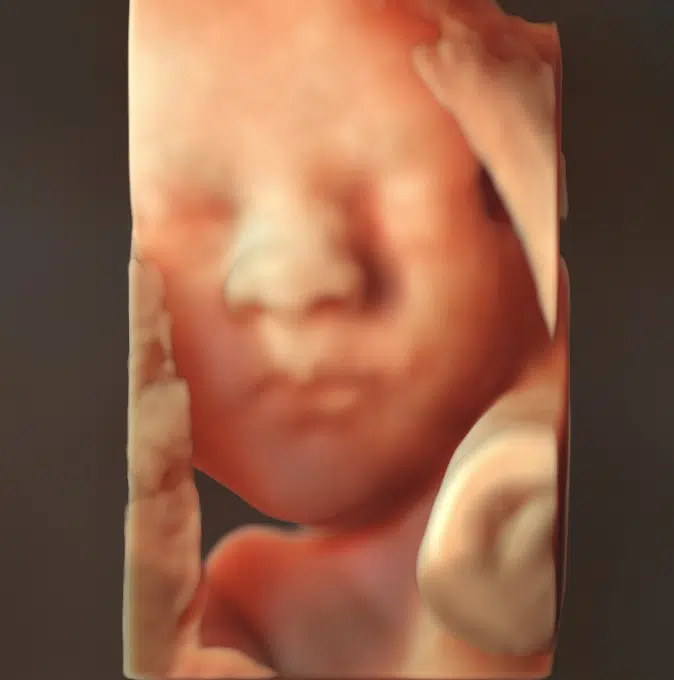

- I 3D ser du barnet, som det rigtigt ser ud inde i maven: Man kan se ansigtstræk, fingre, tæer og navlesnor. Sætter man 4D til, så filmer man og får bevægelser med.

En 3D-scanning giver dig mulighed for at komme endnu tættere på dit barn og opleve de små detaljer, der gør netop jeres barn unikt. Med naturlig 3D og HDlive får du billeder, som giver et livagtigt indtryk – næsten som at se dit barn i virkeligheden.

Når vi tilføjer den fjerde dimension (4D), bliver oplevelsen endnu mere levende, fordi du kan se dit barn bevæge sig. Ligger barnet godt, kan du måske opleve et smil, et gab, en lille hånd i munden eller andre personlige bevægelser.